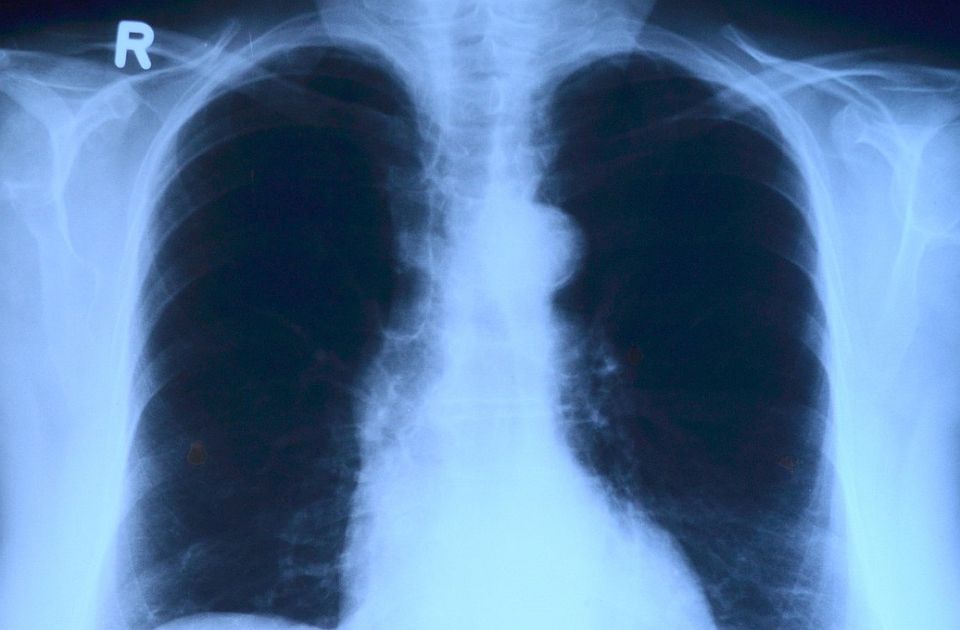

Foto: Pixabay